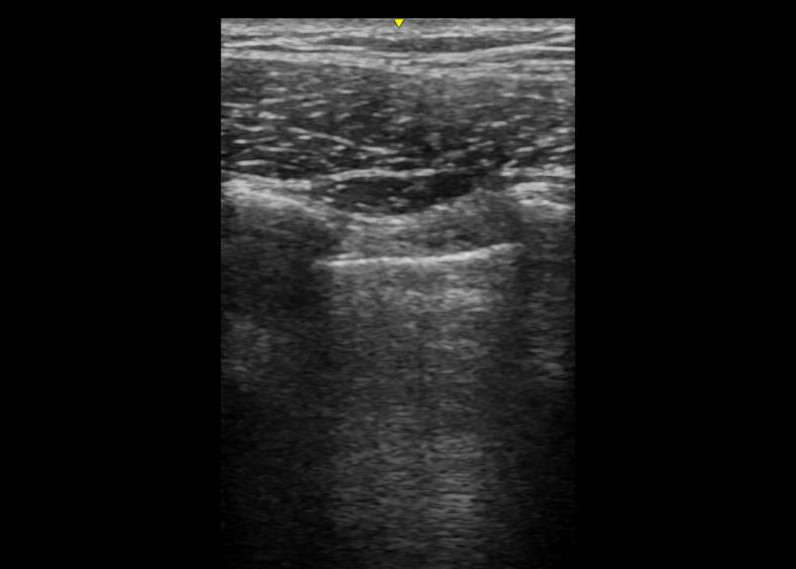

Below are examples of images obtained with the probe in the conventional orientation – perpendicular to the ribs with the probe maker up. Notice how much clearer the lung sliding is in shallow image taken with the linear probe.

Specifically, if you are looking for lung sliding, you need to use a setting with very little depth so that the pleura is prominent on the screen. A linear probe is ideal, but a curvilinear probe with the depth dialed way down is fine as well.